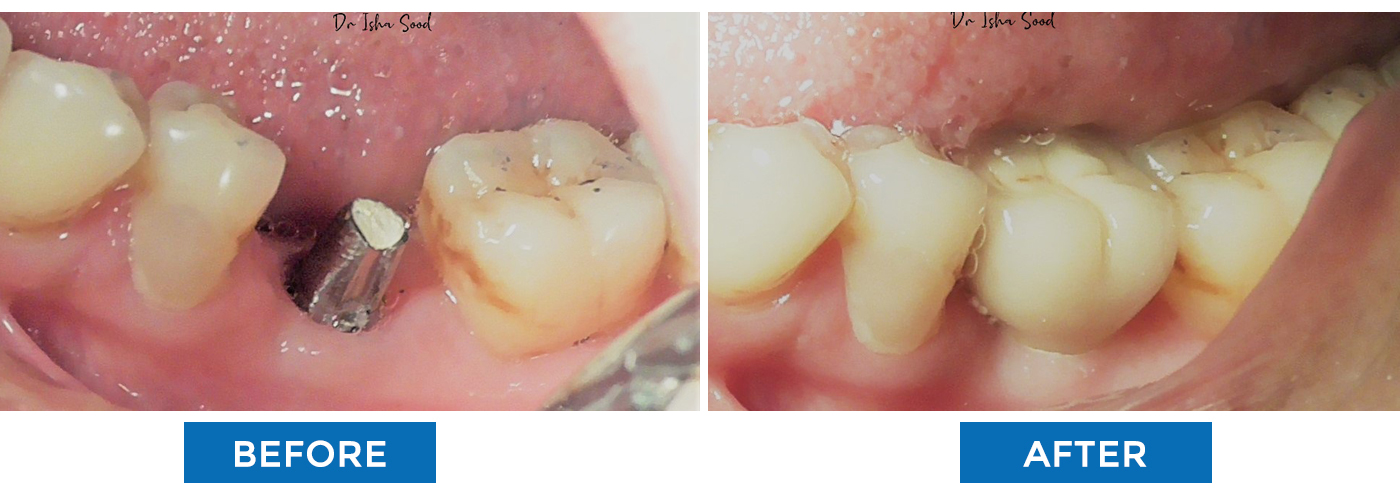

Missing Teeth Replacement

With Dental Implant

Missing Teeth Replacement With Dental Implant

Missing Teeth Replacement With Dental Implants